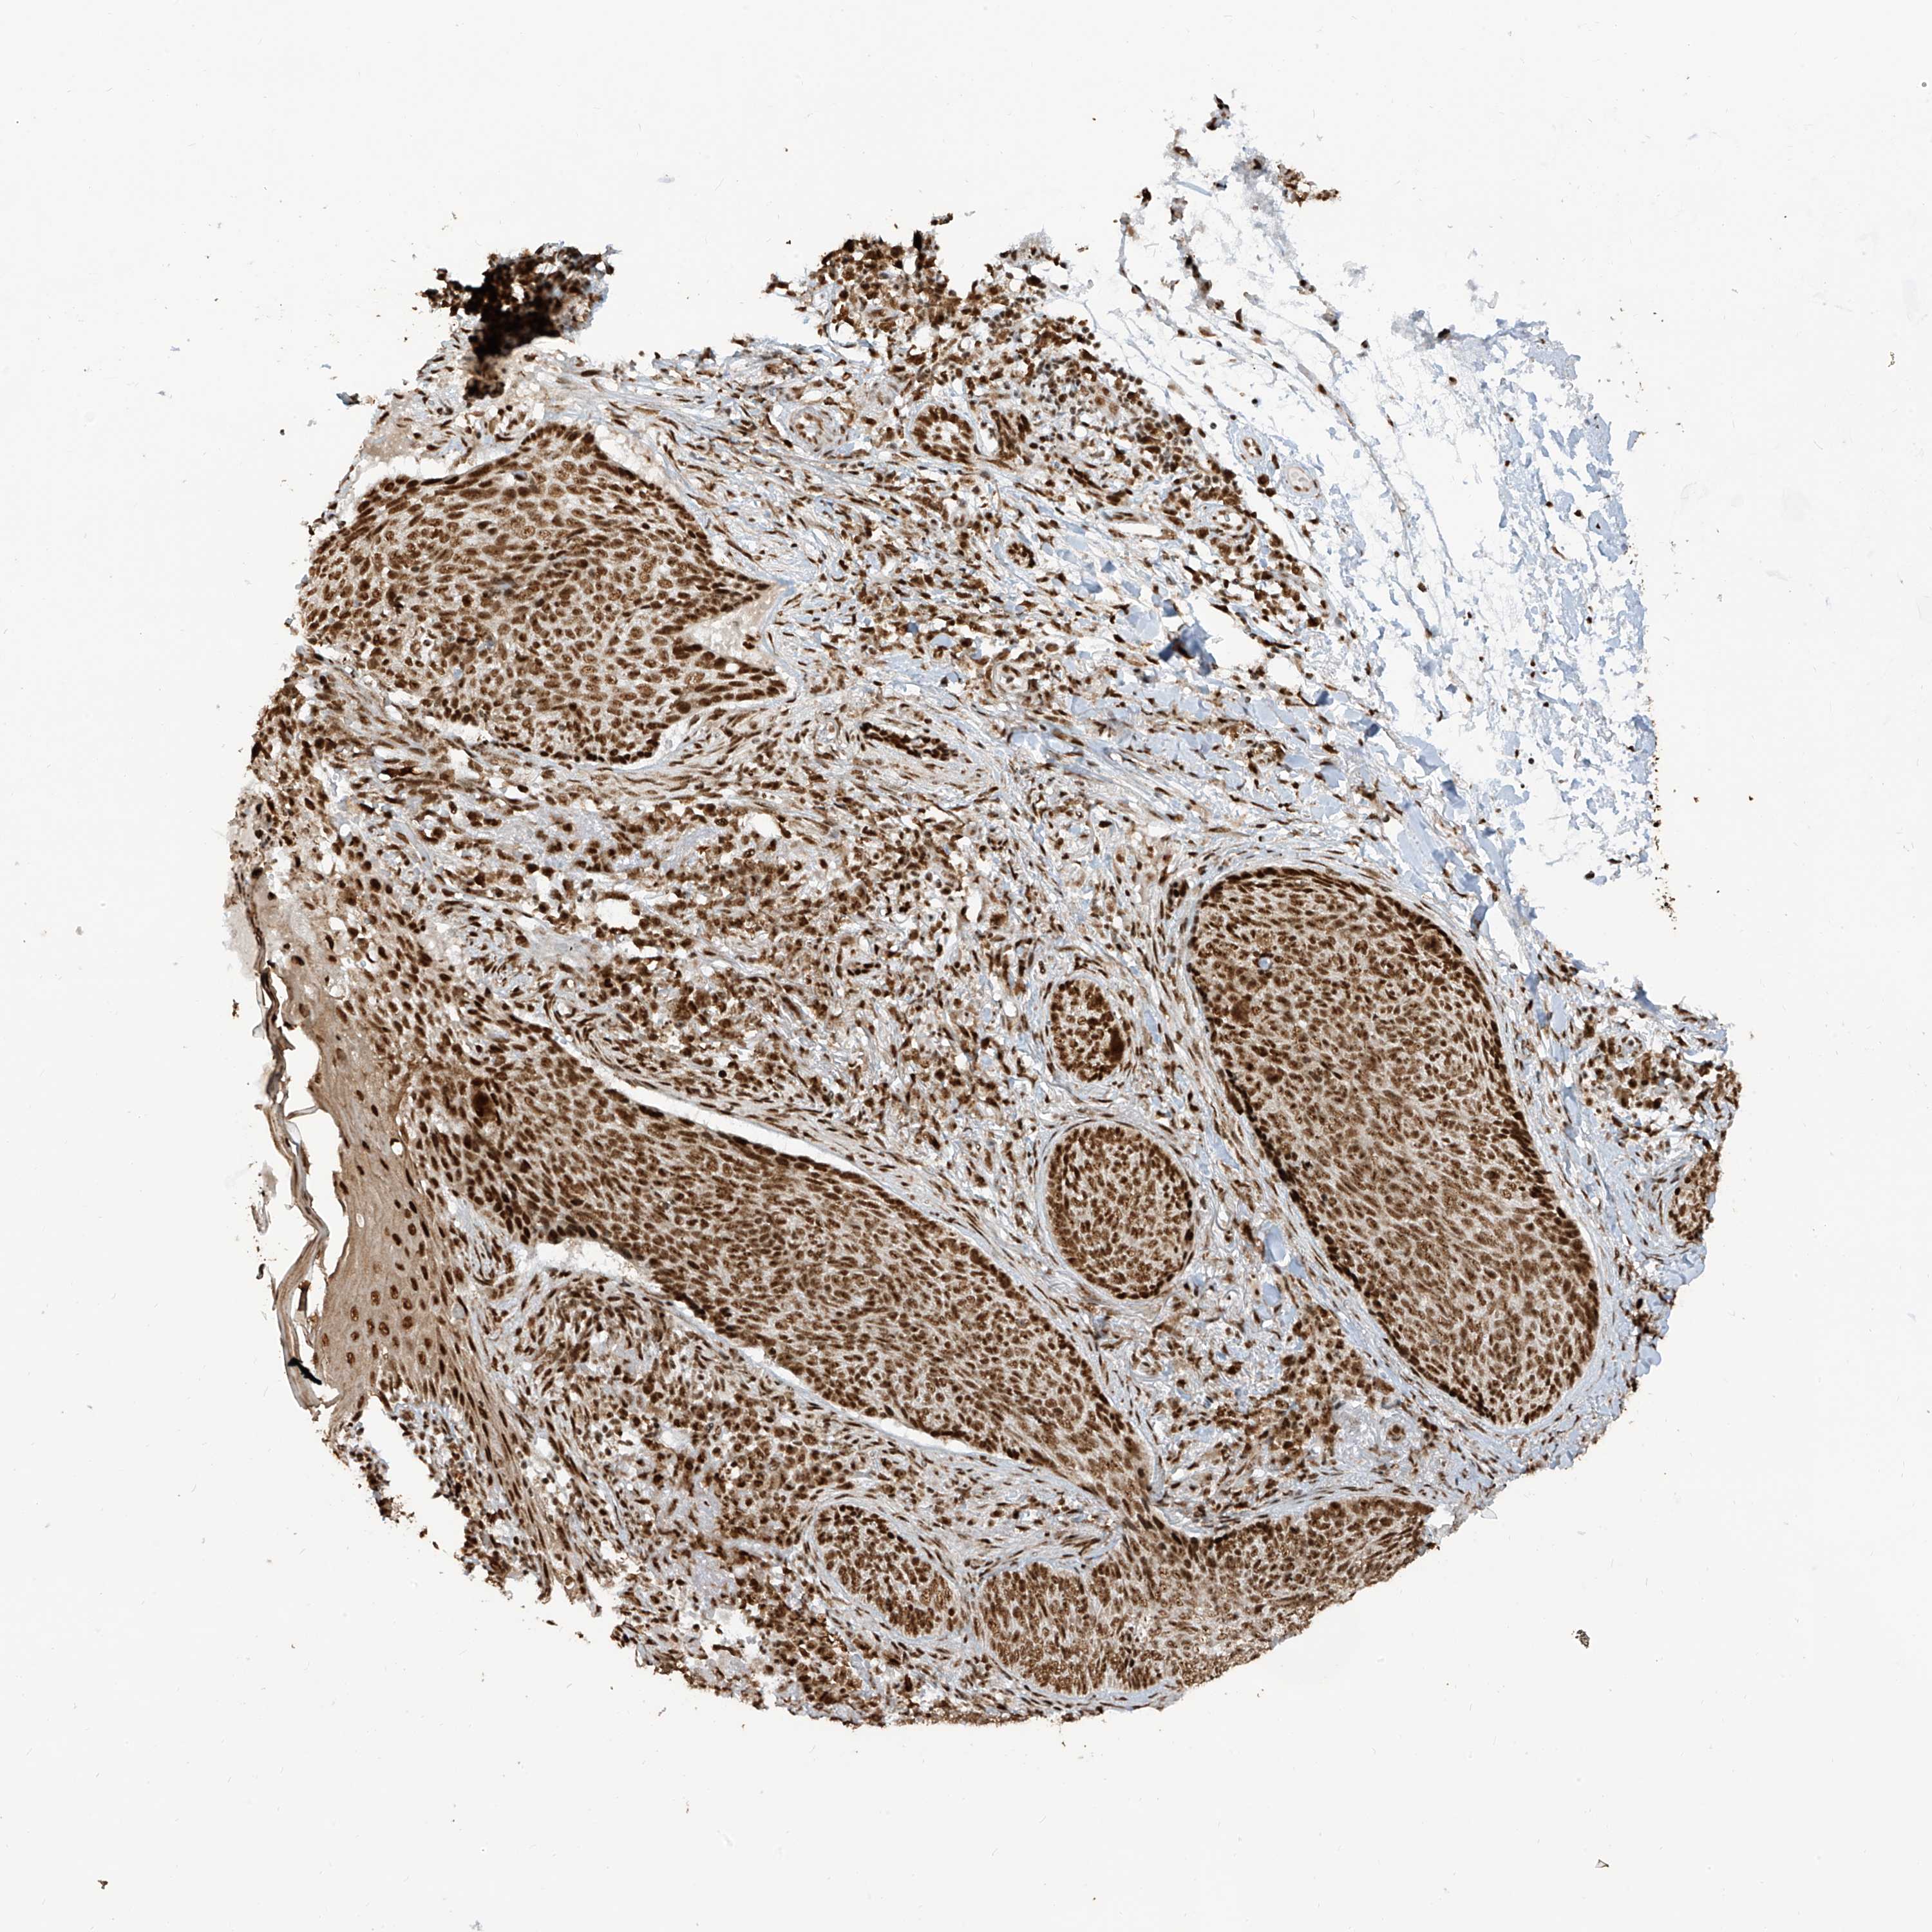

SKIN CANCER - Protein expressioni

A mouse-over function shows sample information and annotation data. Click on an image to view it in a full screen mode. Samples can be filtered based on level of antibody staining by selecting one or several of the following categories: high, medium, low and not detected. The assay and annotation is described here.

Each image is clickable and will lead to virtual microscopy that enables deeper exploration of all samples and also displays staining intensity scores, fraction scores and subcellular localization as well as patient and tissue information for each sample.

Antibody HPA034669

Staining

High

Intensity

Strong

Quantity

>75%

Location

Nuclear

Basal cell carcinoma